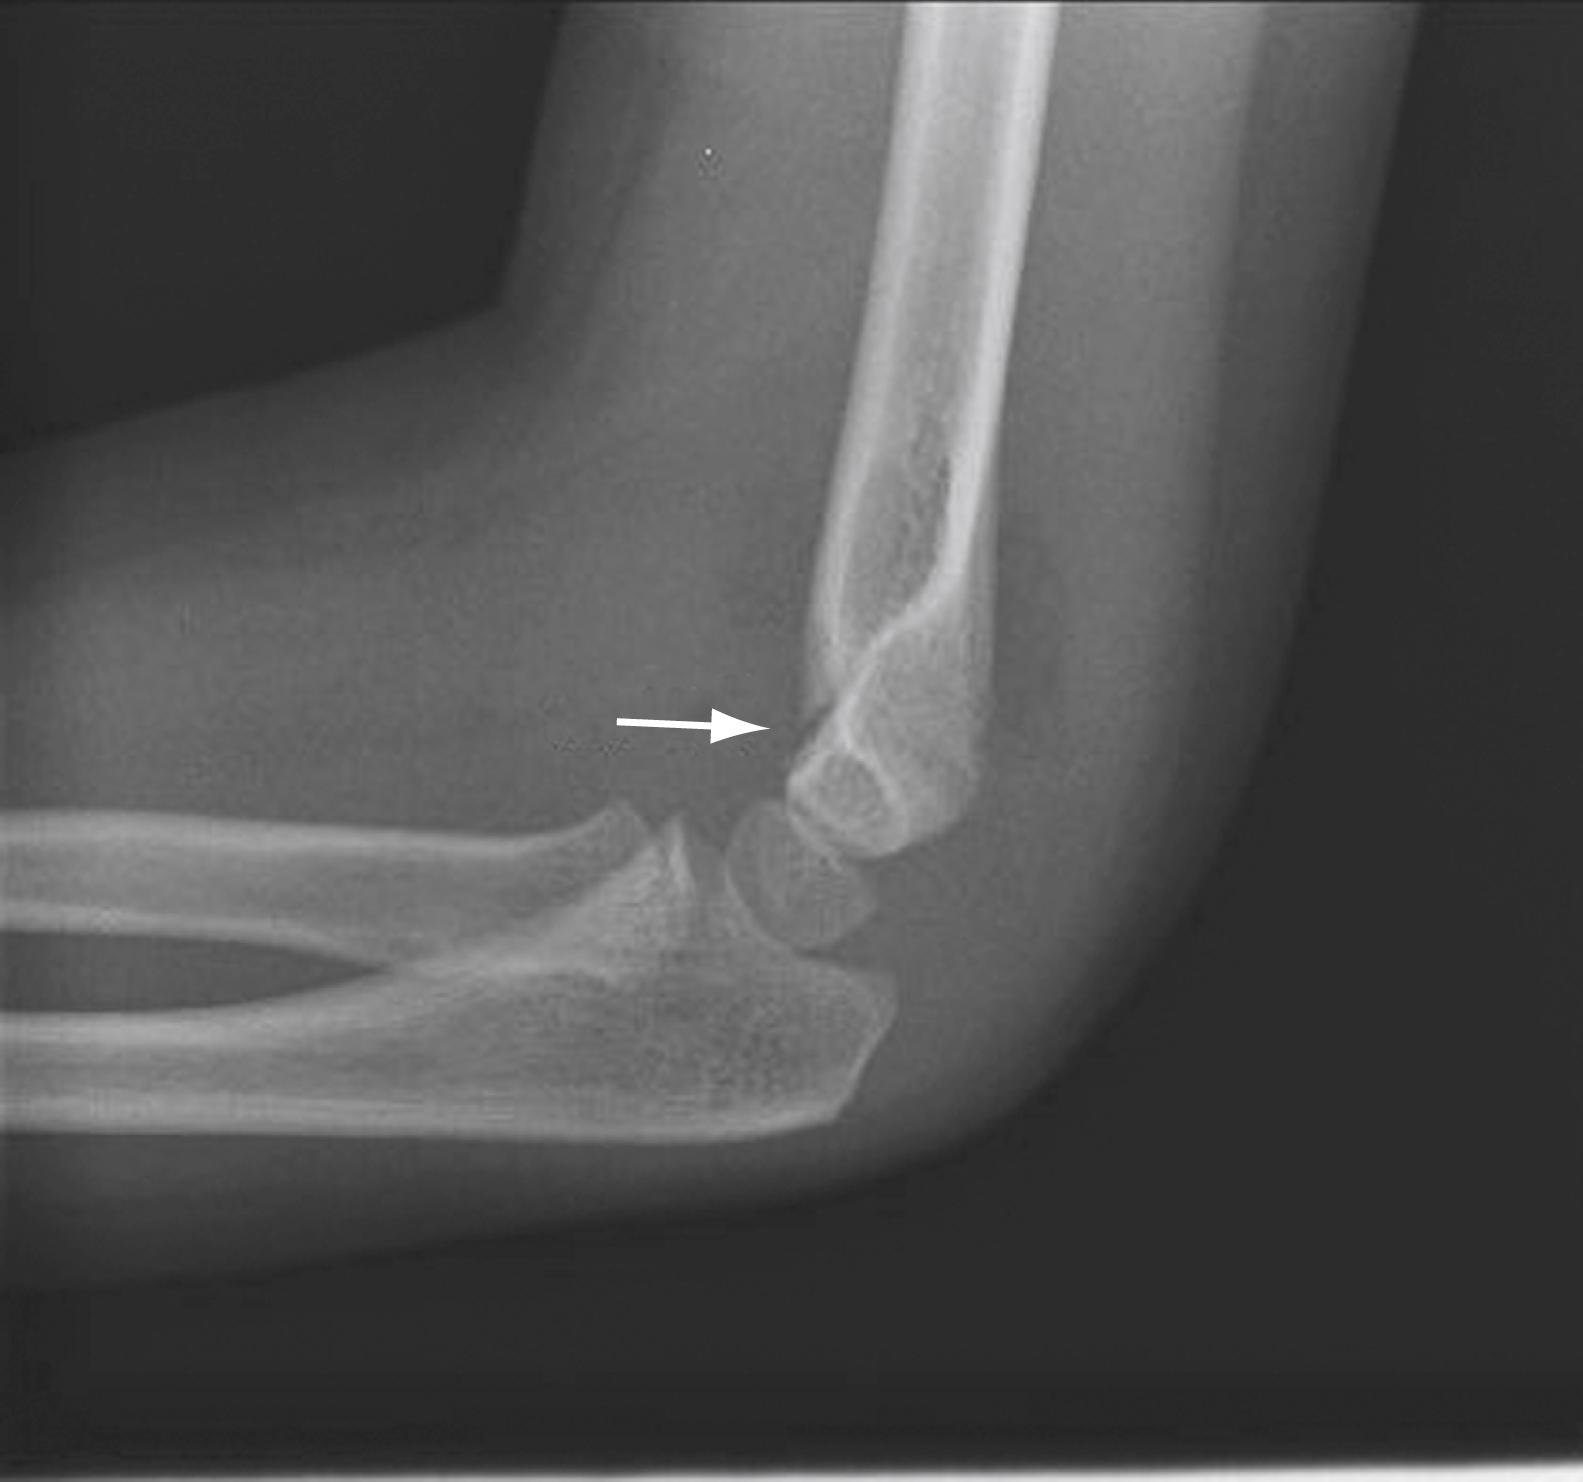

Fig. 44.11, Supracondylar fracture (arrow) with anterior and posterior fat pad.

Extension supracondylar fractures occur as a consequence of a fall on the outstretched hand when the elbow is either fully extended or hyperextended (e.g., a fall off the playground “monkey bars”). The strong action of the triceps tends to pull and displace the distal fragment in a posterior and proximal direction. In children with extension-type supracondylar fractures, the arm is held at the side and has a characteristic S-shaped configuration, whereas with flexion-type supracondylar fractures, the forearm is supported with the opposite hand with the elbow flexed to 90 degrees. There may be anterior angulation of the sharp distal end of the proximal fragment into the antecubital fossa, which could injure the brachial artery and median nerve ( Fig. 44.10 ). In most cases, however, the brachialis muscle protects the anterior neurovascular structures from injury. Because this fracture primarily occurs in children, 25% of supracondylar fractures are of the greenstick variety, with the posterior cortex remaining intact. Subtle changes (e.g., the presence of a posterior fat pad or an abnormal anterior humeral line) may be the only radiographic clues to the presence of a fracture ( Fig. 44.11 ). Ten percent of children lose the radial pulse temporarily, most often as a result of swelling and not direct brachial artery injury. Fracture reduction, avoiding flexing the elbow more than 90 degrees, and elevating the arm help prevent secondary obstruction to arterial flow. Nerve injuries occur in approximately 10% of these injuries, but the incidence increases to a range of 20% to 50% with increasing severity of fracture displacement. , The anterior interosseous nerve is the most commonly injured, followed by the radial, median, and ulnar nerves. Most deficits seen at the time of injury are neurapraxias that resolve with rest and conservative management. Motor function returns within 7 to 12 weeks, whereas recovery of sensation may take over 6 months, though the recovery of injuries with multiple nerve injuries may take longer than that of isolated nerve injuries. ,

Two diagnostic aids in evaluating for possible supracondylar fractures include using the anterior humeral line and evaluation of Baumann’s angle. The anterior humeral line is a line drawn on a lateral radiograph along the anterior surface of the humerus through the elbow. Normally, this line transects the middle third of the capitellum ( Fig. 44.12 ). With an extension supracondylar fracture, this line either transects the anterior third of the capitellum or passes entirely anterior to it. An abnormal relationship between the anterior-humeral line and capitellum may be the only radiographic evidence of a minimally displaced supracondylar fracture and is a presumptive finding of a fracture. Baumann’s angle is the intersection of a line drawn on the anteroposterior film through the midshaft of the humerus and the growth plate of the capitellum defines an angle of approximately 75 degrees ( Fig. 44.13 ). Radiographic evaluation of the elbow in children is challenging because of the presence of multiple ossification centers ( Fig. 44.14 ). Comparison views of the uninjured elbow are often helpful in distinguishing fractures from the normal epiphyses and ossification centers. Table 44.2 lists the typical age of first appearance and fusion of ossification centers.

Fig. 44.12, (A) A line drawn down the anterior surface of the humerus on a lateral film should transect the middle third of the capitellum. (B) With an extension supracondylar fracture, the line passes more anteriorly.